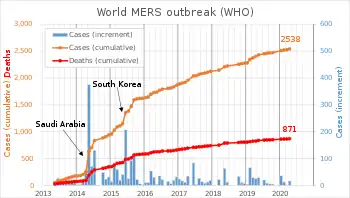

MERS has had a relatively low population-wide reproduction number in previous outbreaks, but such outbreaks have occurred due to superspreading events.[62] Total laboratory-confirmed cases of MERS world-wide per year have been as follows:[63][64]

| 2012 | 2013 | 2014 | 2015 | 2016 | 2017 | 2018 | 2019 |

|---|---|---|---|---|---|---|---|

| 14[64] | 100[64] | 381[64] | 492[63] | 249[63] | 250[63] | 147[63] | 212 (as of 12 Dec)[65] |